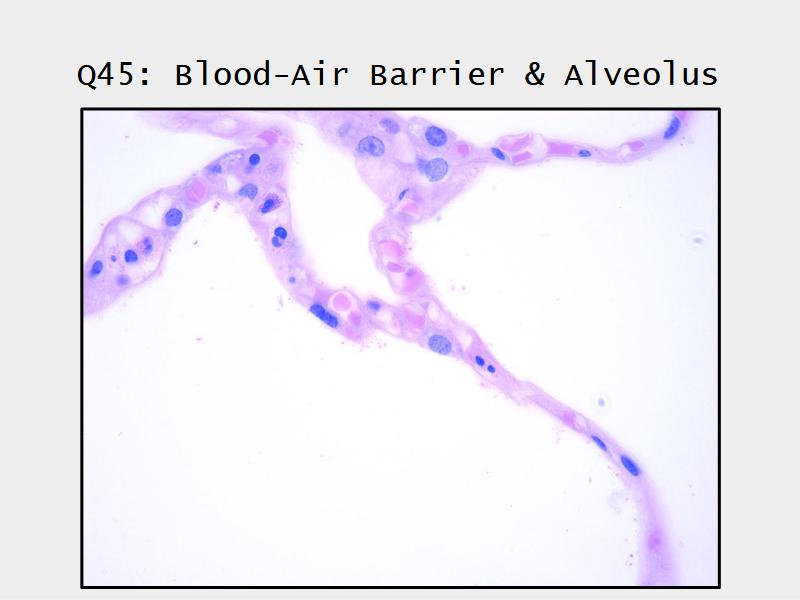

Components of the Blood-Air Barrier?

What other barrier systems are found in the body?

What are the purpose of each of these barrier systems? Connected with physiology will unlock the pathology.

Barriers

- Blood-air